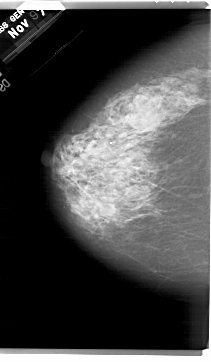

A_1416_1.RIGHT_MLO

RIGHT_MLO LINES 6691 PIXELS_PER_LINE 4081 BITS_PER_PIXEL 12 RESOLUTION 43.5 OVERLAY